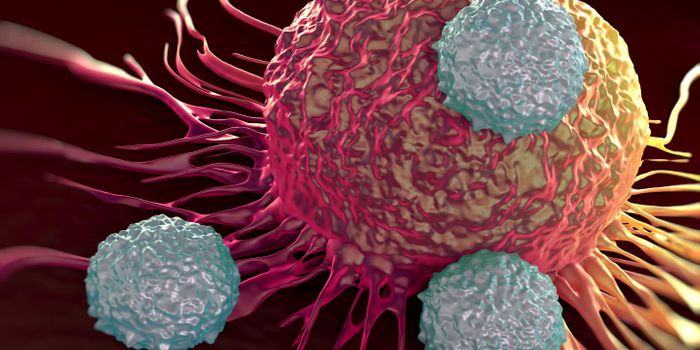

OCT 14, 2016ImmunologyEnhancing a cancer patient’s own T cells to reduce tumor growth is an up-and-coming cancer therapy that is being u ...

NOV 29, 2023CancerThe CAR-T Revolution: Developing T Cells into Cancer Assassins Cancer has long been a formidable foe, but recent ...

MAY 22, 2017ImmunologyThree new approaches to anticancer drug therapy were combined in a recent study to simultaneously maximize destruction o ...